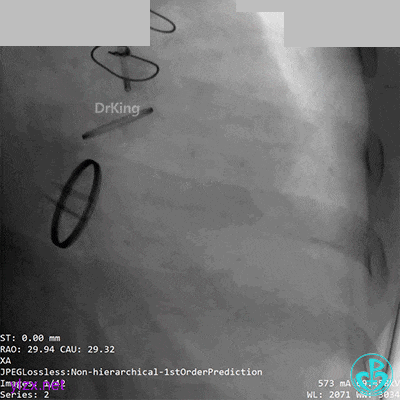

07 10天后复查造影

前降支血栓消失,回旋支恢复3级血流。回旋支夹层?血栓?

没有进一步处理。